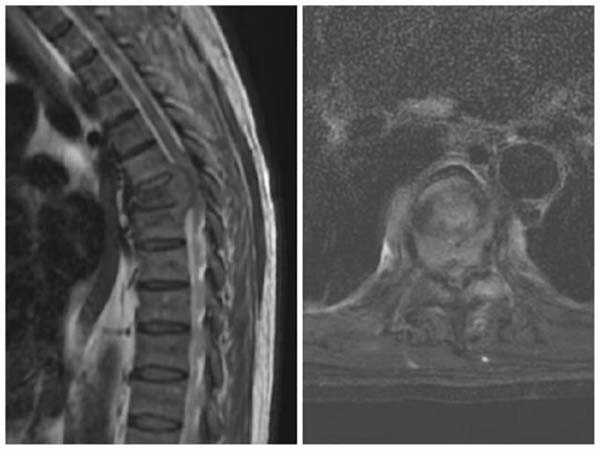

图2 术中氩氦刀冷冻消融灭活胸椎转移瘤,术后复查MRI提示氩氦刀冰球消融覆盖病变区域

该患者经胸椎穿刺活检,确诊为肾癌胸椎转移。考虑到一期手术切除肿瘤会导致大量出血,而且单纯后路手术难以完整切除肿瘤,经全科讨论后最终制定了这一联合治疗方案。手术过程中,医生在C臂引导下将氩氦刀精准插入胸椎椎体病灶,通过快速冷冻和复温,成功地将肿瘤组织彻底摧毁,同时最大限度地保护了周围正常组织。联合后路椎管减压术和脊柱内固定术,有效解除了脊髓压迫, 并重建了脊柱稳定性,患者的疼痛和不全瘫症状得到明显改善。此次治疗也为二期行前路肿瘤切除、骨水泥或钛网重建前柱奠定了良好基础。